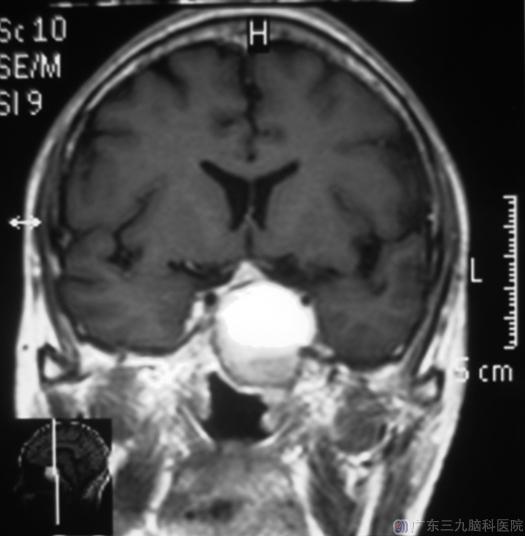

一周前他开始出现头痛,以左侧颞部胀痛为主,广东三九脑科医院头颅CT提示:鞍区占位性病变;头颅MR检查:蝶窦-鞍区示一囊肿异常信号影,大小约3.4cm×3.3cm×3.2cm,垂体及视交叉向上受推压。